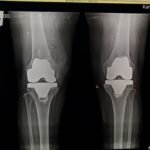

Knee replacement surgery involves removing the arthritic bone from the thigh bone (femur) and shin bone (tibia). The removed bone is replaced with metal and special plastic. During the surgery, the arthritic bone underneath the knee cap is also removed and replaced with a plastic button. The prosthesis utilizes the patient’s native ligaments and muscles for movement and stability.

Knee replacements consist of a few different parts. The femoral component is made of cobalt chrome, the tibial component is made of titanium and the insert is composed of highly cross-linked polyethylene. The patellar is resurfaced with a button made of highly cross-linked polyethylene also.